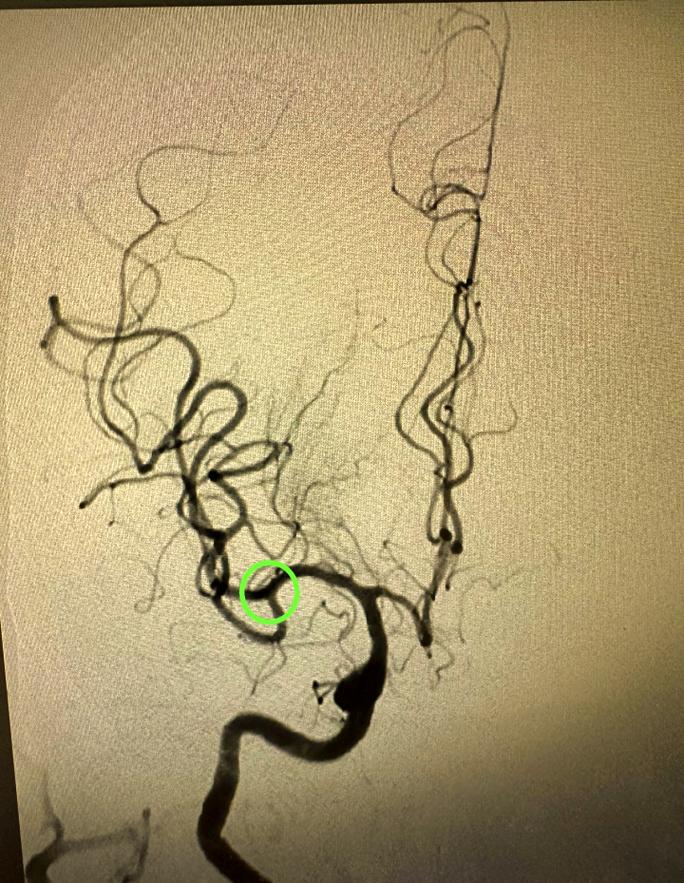

(图片来源网络,侵删)

- 静脉溶栓时间窗: 发病后 5小时内,这是通过注射药物溶解血栓的关键时期,越早越好。

- 动脉取栓时间窗: 发病后 6-24小时内(需经过严格影像学评估),对于大血管堵塞的患者,可以通过介入手术直接取出血栓,恢复血流。

患者被送到医院后,医生会争分夺秒地进行头颅CT等检查,以判断是否符合溶栓或取栓条件。